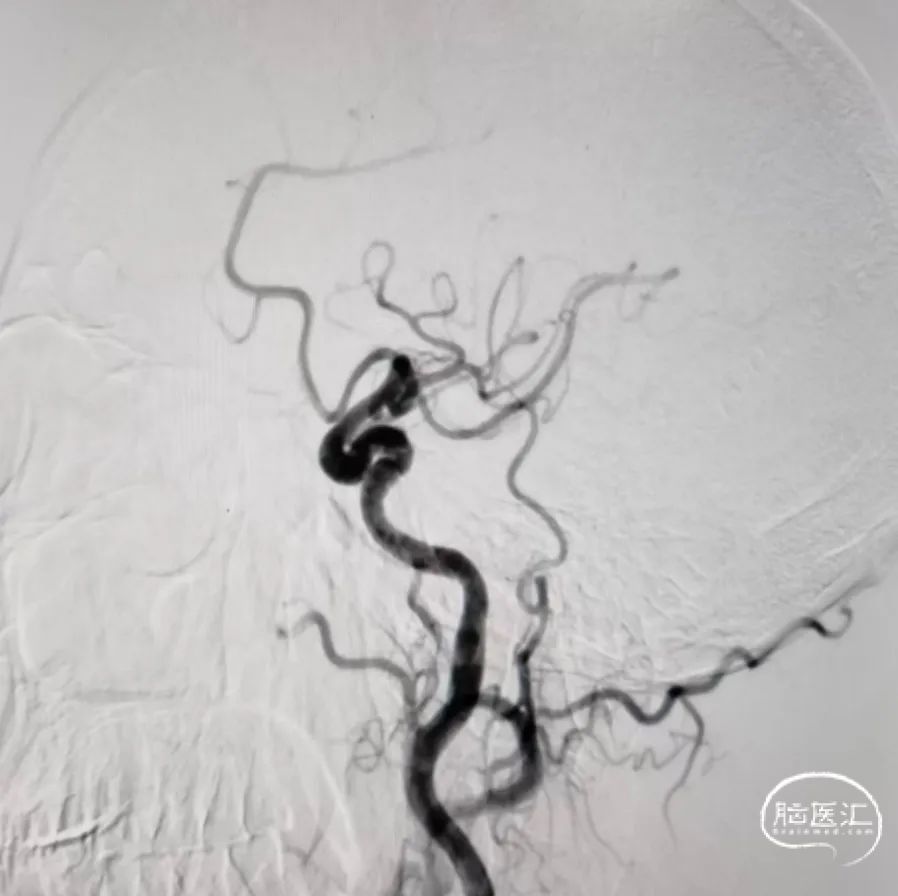

➢ 术前造影:

正位

侧位